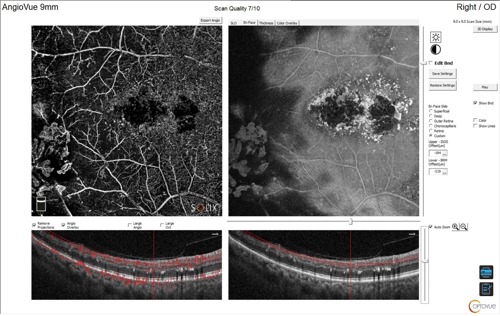

Optical coherence tomography (OCT) and OCT angiography (OCT-A) were performed using the Optovue Solix Spectral Domain OCT system (Visionix) to assess for the presence of neovascularization and macular edema. Due to the equatorial location of the anomalous vasculature, 9x9 mm and 12x12 mm OCT-A were selected.

The utilization of OCT-A was instrumental in confirming the diagnosis of proliferative diabetic and sickle cell retinopathy and identifying associated macular edema. Employing advanced imaging technologies enhances diagnostic accuracy and supports improved clinical decision-making.